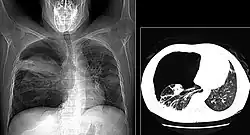

The diagnosis can be confirmed by the characteristic appearance of the chest X-ray and an arterial oxygen level (PaO2) that is strikingly lower than would be expected from symptoms. Gallium 67 scans are also useful in the diagnosis. They are abnormal in about 90% of cases and are often positive before the chest X-ray becomes abnormal. Chest X-ray typically shows widespread pulmonary infiltrates. CT scan may show pulmonary cysts (not to be confused with the cyst-forms of the pathogen).

These chest radiographs are of two patients. Both show ground glass opacities. The left X-ray shows a much more subtle ground-glass appearance while the right X-ray shows a much more gross ground-glass appearance mimicking pulmonary edema.[7] -

High-resolution computed tomography (HRCT) showing ground-glass attenuation with a geographic or mosaic distribution.[7] -